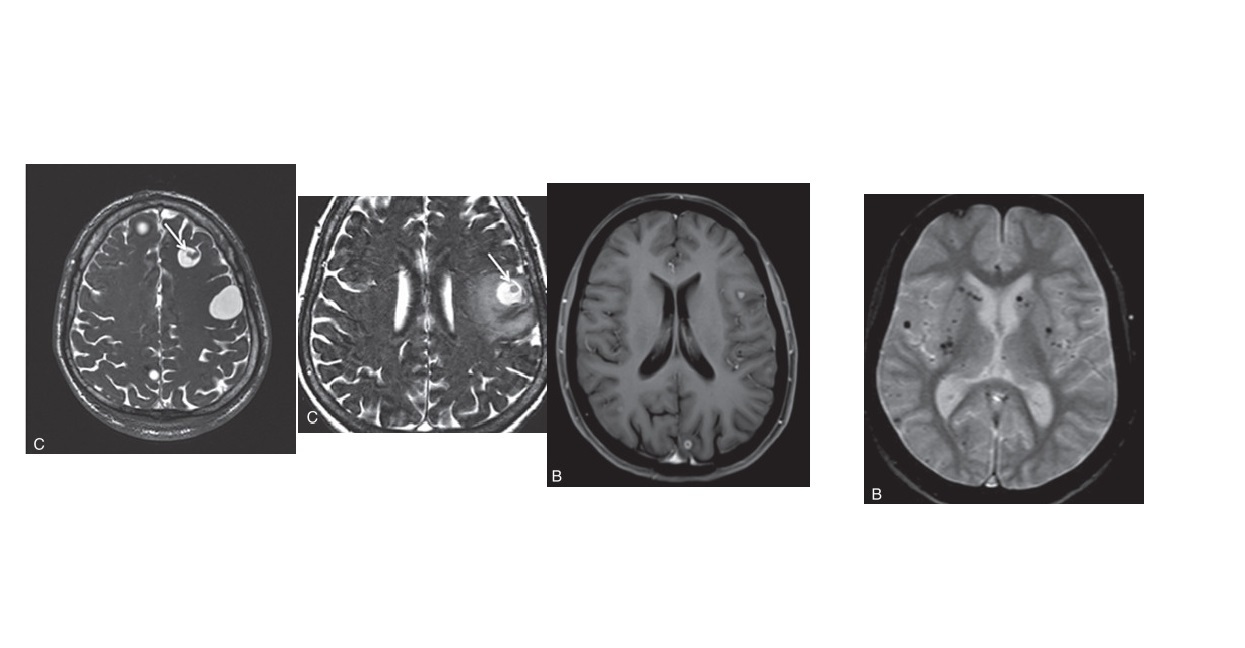

4 stages of Neurocysticercosis (VCGN) ?

A

Vesicular -

Thin walled cyst - CSF pattern. No pericystic oedema. (Low T1/T2)

scolex (hole with dot appearance)

Colloidal -

Hyperdense cyst - proteinaceous fluid) (High T1/T2) . **pericystic oedema and enhancement **

scolex (hole with dot appearance) can persist

Granular -

Cyst shrinks, small ring-enhancing or solid nodule enhancement. less pericysitc oedema

Nodular -

Small calcified lesion. no oedema or enhancement. hypointense on all sequences due to calcification